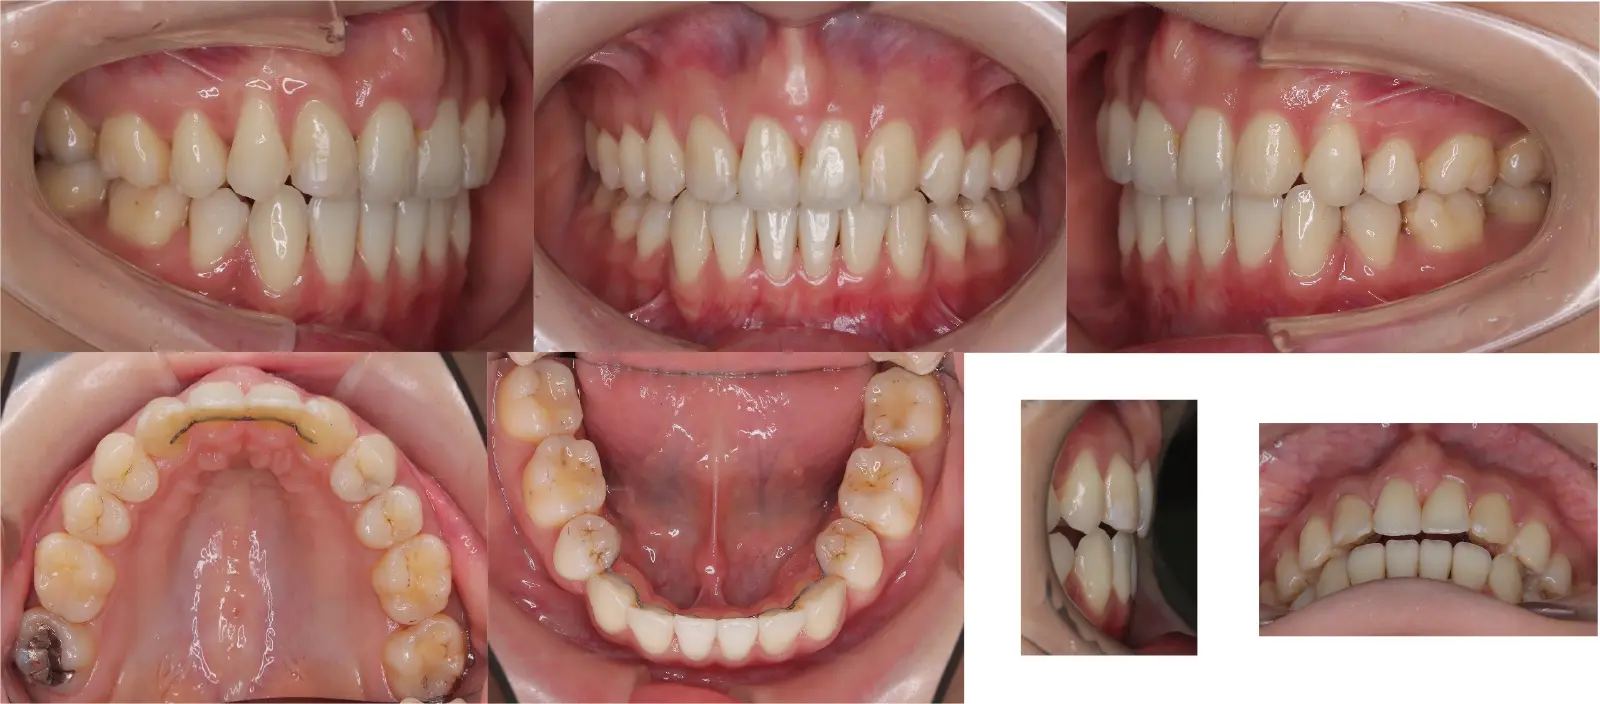

アングルⅡ級叢生を伴う上顎前突症

- 主訴

出っ歯

- 年齢

20代

- 治療期間

2年6ヶ月

- 治療回数

29回

- 治療に用いた主な装置

カスタムメイド型リンガルブラケット矯正装置 (WIN)

- 治療費

1,400,000円(税別)トータル料金

- 抜歯部位

上顎の中切歯が失活歯で、根尖病変が存在したため、上顎中切歯と下顎左右側第一小臼歯を抜歯。